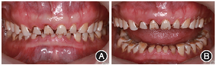

干扰等[9],这两种情况均易导致前牙的重度磨耗(图1)。

患者前牙重度磨耗口内像 A:全牙列正面咬合像;B:全牙列正面非咬合像

患者前牙重度磨耗口内像 A:全牙列正面咬合像;B:全牙列正面非咬合像(2)磨损(abrasion):是指牙齿受到除牙齿外的其他物体的机械性摩擦,导致牙齿硬组织进行性丧失。常见磨损原因包括咀嚼硬食习惯、不良刷牙习惯以及咬硬物习惯等;其含义不同于作为此类疾病统称的牙齿磨损。